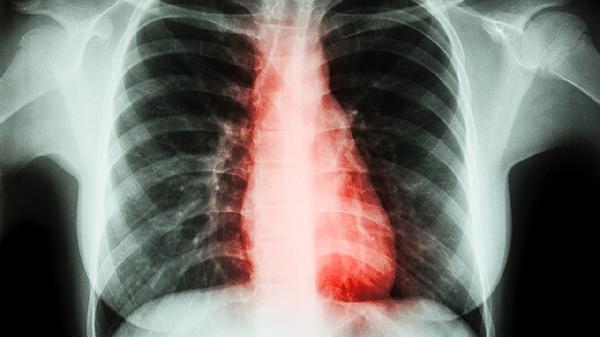

4、放射性肺炎

胸部放疗后出现的放射性肺炎可选用此药。放射性肺炎是放疗常见并发症,表现为干咳、胸痛、呼吸困难。养阴清肺合剂能减轻放疗引起的肺组织损伤,但需与泼尼松片等抗炎药物配合使用。此类患者需定期复查肺部CT。